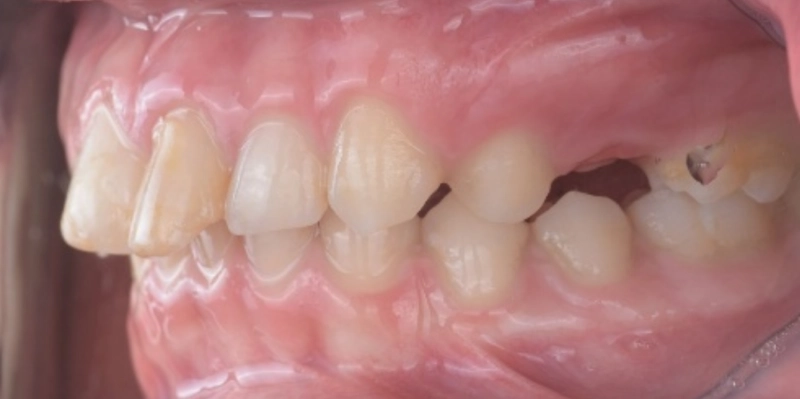

תמונות לפני ואחרי טיפול

לפני

ק.ר., בן 12, הגיע למרפאה עם מקרה אורתודונטי מורכב, שכלל שילוב של בעיה סגרית, צפיפות דנטלית ואתגר אסתטי משמעותי באזור הקדמי. בבדיקה נמצא סגר עובר אופקי מוגדל, סגר אסימטרי עם יחסי קלס 2 בצד ימין באזור הטוחנות, יחס טוחנות תקין בצד שמאל, אך יחסי קלס 2 באזור הניבים בשני הצדדים. בנוסף נצפתה צפיפות באזור החותכות העליונות, עם חפיפה בין שיניים 11 ו 21, וכן צפיפות גם בקשת התחתונה.

מעבר למורכבות האורתודונטית, האתגר המרכזי במקרה זה היה שן 21, החותכת המרכזית העליונה השמאלית, שעברה חבלה, טופלה בטיפול שורש, שינתה צבע ויצרה פגיעה אסתטית משמעותית. מצב זה חייב תכנון זהיר במיוחד, משום שהיה צורך לשפר את הסגר, לפזר את הצפיפות וליישר את השיניים, אך לעשות זאת תוך הימנעות מהפעלת כוחות על השן הפגועה בשלבים הראשונים, כדי לא לסכן את מצבה ואת המשך שרידותה.